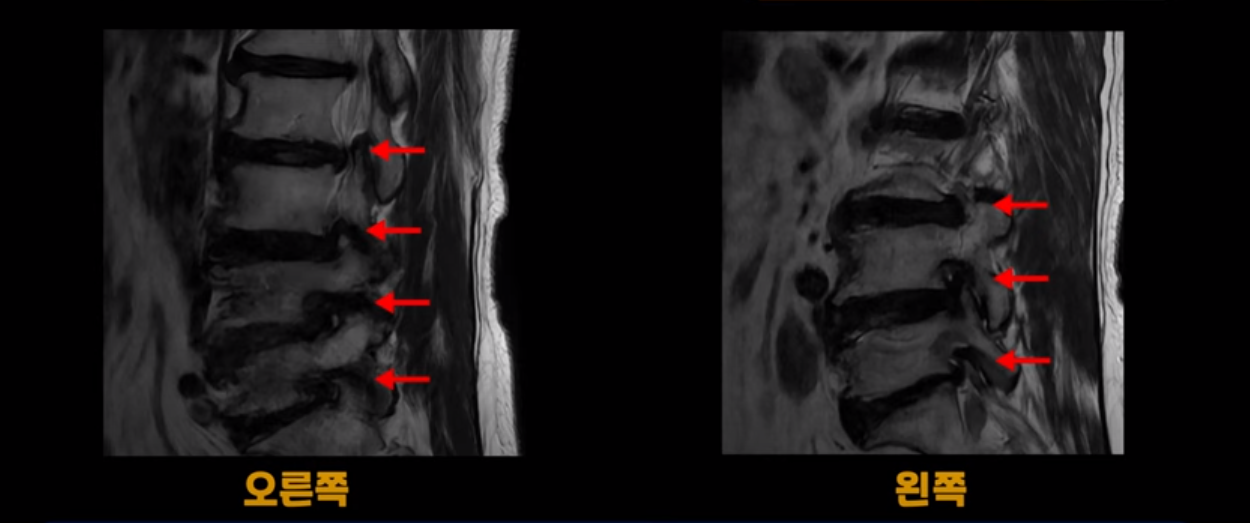

MRI 보시면 (2-8) 허리의 5마디가 전부 다 심하게 퇴행되어 있습니다.

5마디 전부 다 심한 중심성 협착이 있습니다.

1번 2번,

2번 3번,

3번 4번,

4번 5번,

5번 6번

이렇게 모두 다 심하게 막히는 경우는 드문데요. 또한 오른쪽, 왼쪽 신경이 빠져나가는 추간공도 다 심하게 막혀있습니다.

오른쪽, 왼쪽 이렇게 신경 구멍들이 다 좁아지고 신경이 눌리니까 양쪽 다리가 발바닥까지 아파서 걷기 어렵고 양쪽 발이 10년 넘게 시린 겁니다. 당연히 수술해서 눌린 신경을 풀어줘야 한다고 들으셨는데요. 이런 환자분을 어떻게 수술 없이 치료할까요? 지금부터 설명해 드립니다.